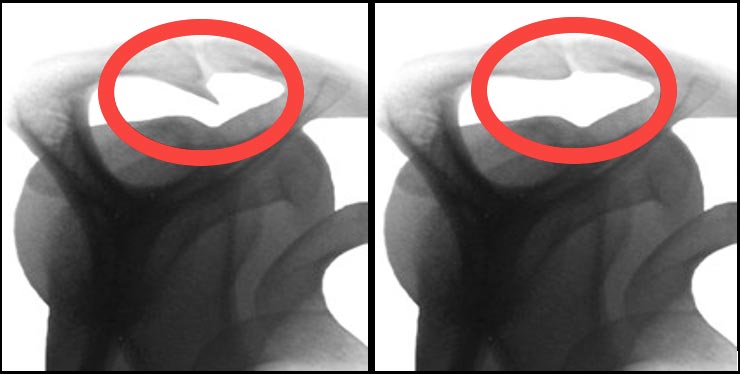

Impingementsyndrom: Ursachen und Behandlung

Beim Impingementsyndrom entsteht unterhalb des Schulterdaches eine Verengung, die Sehnen der Rotatorenmanschette und Schleimbeutel betrifft – oft durch einen vorderen Knochensporn verursacht.

Wenn konservative Therapien wie Krankengymnastik über Monate keine Besserung bringen, kann eine arthroskopische Operation helfen. Dabei werden entzündete Schleimbeutel und knöcherne Engstellen entfernt, um den Raum unter dem Schulterdach zu erweitern. So wird das freie Gleiten der Sehnen ermöglicht und weitere Schäden verhindert.